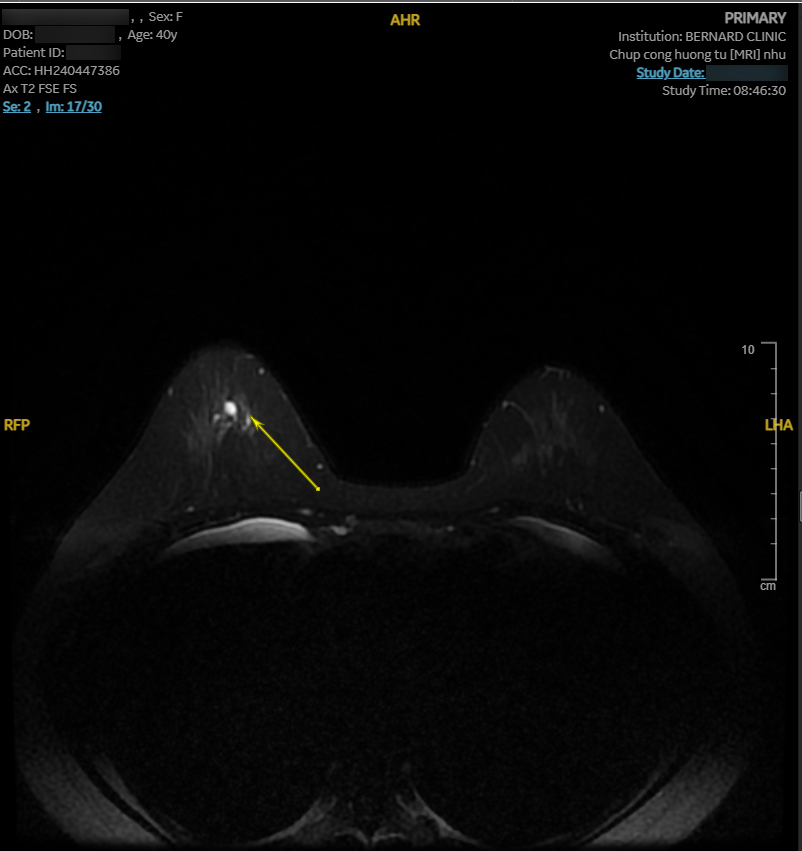

Hình ảnh MRI cho thấy nhiều bất thường. Vú phải có nang vú vị trí 6 giờ, cách núm vú 3cm, d-7mm, phân loại BI-RADS 2. Vú trái có bất thường tín hiệu diện rộng 1/2 dưới (6 - 8 giờ), giới hạn bờ kém rõ, tổn thương dạng đám/nốt/đường, BI-RADS 4.

Nhận thấy hình ảnh MRI bất thường, Hội đồng Y khoa Bernard lập tức chuyển hội chẩn “second opinion” với các Giáo sư Chẩn đoán hình ảnh của Bệnh viện Đại học Yamanashi (Nhật Bản). Kết luận từ chuyên gia Nhật tương đồng: tổn thương trong ống tuyến - nghi ung thư tại chỗ (carcinoma in situ), BI-RADS 4B.